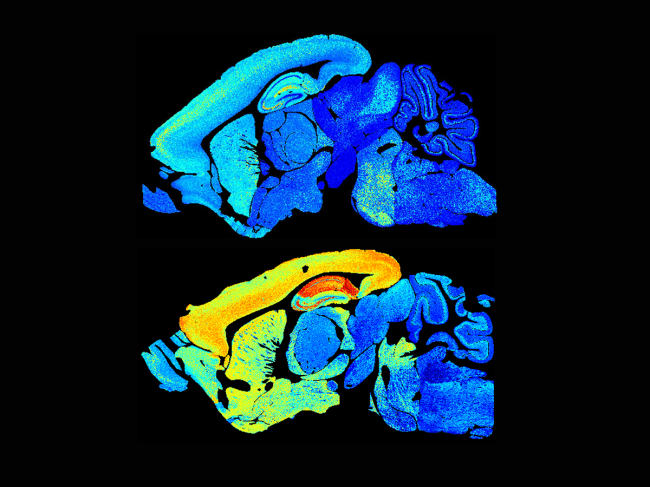

Young and adult mouse brains

Bench Press for June 12, 2020

BioWorld looks at translational medicine, including: Prozac for infectious disease; How CDK comes unglued; Macrophages rewire cholesterol metabolism for bacterial toxin defense; ApoE4’s role in Alzheimer’s blood vessels; HRAS-driven translation helps skin prevent tumors; Discovering pharmacological enzyme activators; Broad-spectrum antiviral has activity against Zika; Lifespan synaptic atlas gives developmental insights; NETS and mets. Read More